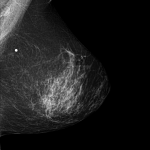

Uma das principais áreas onde a IA tem mostrado grande promessa é no diagnóstico médico. Algoritmos de IA podem analisar grandes volumes de dados, incluindo imagens de exames como tomografias, ressonâncias magnéticas e radiografias, para identificar padrões sutis que podem escapar à detecção humana. Isso pode levar a diagnósticos mais precisos e rápidos, permitindo um tratamento mais eficaz e precoce.

Na imagem abaixo podemos ver como é uma leitura realizada por IA de um exame de mamografia de uma paciente com câncer de mama.